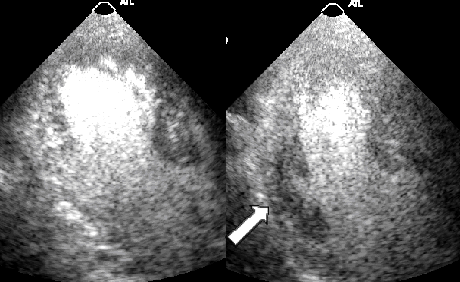

O padrão visual da perfusão miocárdica foi considerado normal quando o contraste, em repouso, distribuiu-se de forma homogênea em todos os segmentos das paredes do ventrículo esquerdo e, principalmente, quando se seguiu de acentuada intensificação deste contraste ao final da administração do nitroprussiato de sódio (Fig. 1).

Imagem de ecocardiograma exibindo um corte 4 câmaras apical - Perfusão miocárdica normal em repouso (esquerda) e após infusão de nitroprussiato de sódio (direita)

Figura 1 – Corte 4 câmaras apical, contendo uma perfusão miocárdica normal em repouso (esquerda) e após infusão de nitroprussiato de sódio (direita)